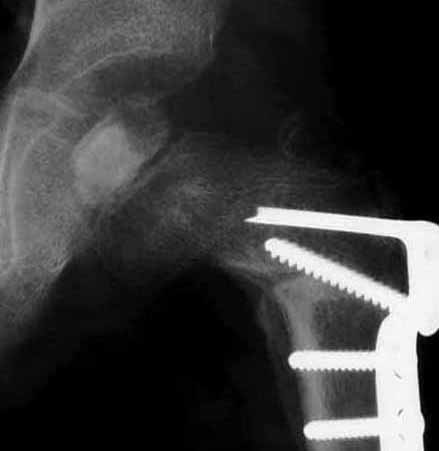

左図は手術前です。骨頭の外側の1部が臼蓋からはみだしています。右図のように骨切りをおこなって、骨頭の向きを変え、はみだした部分までも完全に臼蓋の奥深くに包み込みます。この手術は術前に骨の正確な計測を行い、手術ではその計画を厳密に実行します。皮膚切開の後には、筋肉の剥離、骨の展開、関節包の温存、金属の打ち込む方向、注意深い骨切り、下肢短縮を最小限に押さえる工夫、など、いずれをとっても慣れた術者が行わないと(少なくとも50例の経験は必要)重篤な合併症をおこすことがあります。

最近では固定材料が改良され、強固な固定が可能となりました。したがって、新しいプレートを使って大腿骨単独手術の場合(骨盤手術を合併しない場合)はギブス期間が3週前後に短縮されます。ギブス除去後には座位ならびに松葉づえ歩行が開始されます。